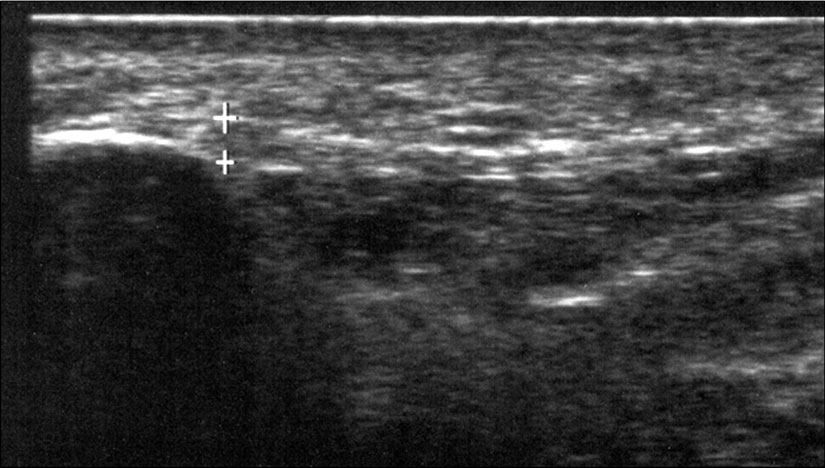

Bildgebung

Die sonographische Diagnostik eignet sich primär zur Erkennung schmerzhafter Prozesse im Verlauf der Achillessehne und kann bei Bedarf durch Röntgen bzw. MRT ergänzt werden. Besonders bei längeren Verläufen und kräftigen spindelförmigen Schwellungen (>9mm, Normwert <5mm) im Bereich der kritischen Zone sollte ein MRT zum Ausschluss von Nekrosezonen und Partialrupturen vor Therapiebeginn veranlasst werden. Die sonographisch leicht zu erfassende Veränderung der Sehnendicke im mittleren Sehnenanteil ist ein guter Indikator für die Schwere der Erkrankung und die Beurteilung des Behandlungsverlaufes. Die sichtbaren Veränderungen am distalen knöchernen Ansatz der Sehne sind diskreter.